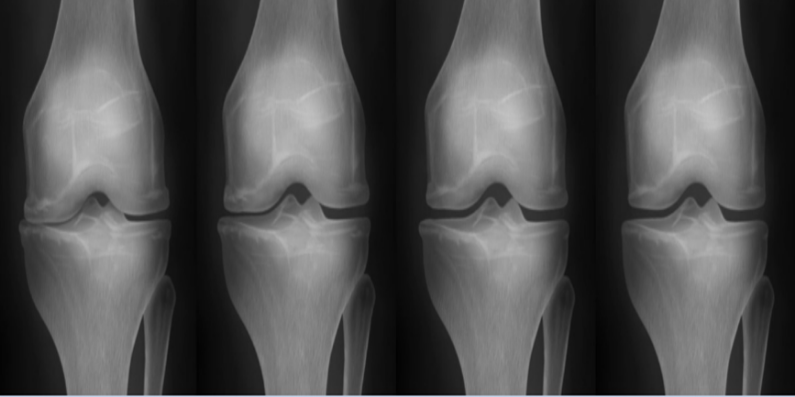

줄기세포 시술 전후 관절 내시경